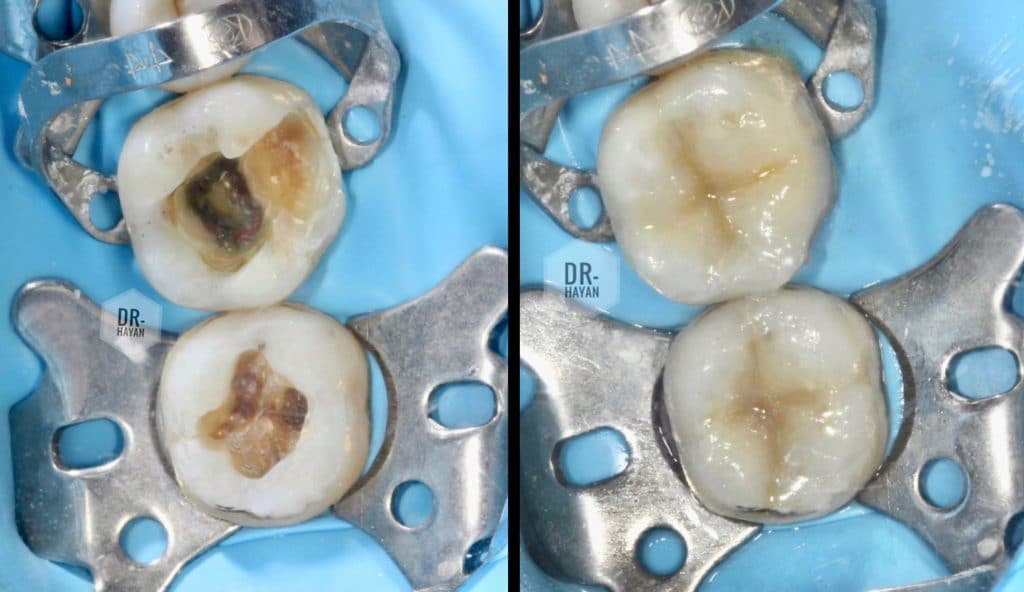

After complete soft caries removal

Amalgam tattoo & hard discoloration dentine on floor of cavity

No need for remove it :

-To save the pulp from irritation due to residual monomer

- natural dentine protection

- After etching dis infected the cavity by CHX

And dry it only

Used dentsply neo st flow

Buccal wall bulding up

Compsite use : dentsply neo spectra ST/ LV

Final anatomy of lower 6